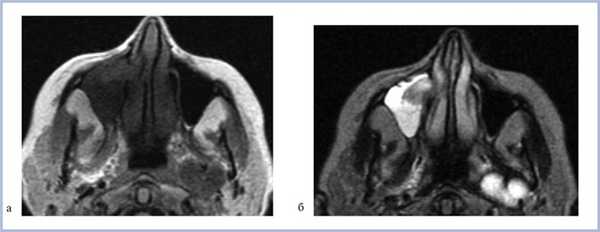

Магнитно-резонансная томография (МРТ) позволяет выявить более «тонкие» изменения в мягких тканях. При подозрении на раннюю стадию грибкового синусита рекомендуется использовать МРТ как метод, наиболее чувствительный к инвазии костной стенки [7]. Но данный метод имеет ряд недостатков: «недостоверность» пространственной анатомии костных структур, трудности выявления костных стенок одонтогенных кист, пломбировочного материала, артефакты от металлических конструкций, а также высокую частоту гипердиагностики и др., которые серьезно ограничивают его применение [8].

При МРТ-исследовании у 8 (80%) больных определялось асимметричное снижение интенсивности сигнала в режиме Т1 от ретромаксиллярной клетчатки, а ее истончение выявилось в 3 (30%) случаях. Изменений со стороны костной стенки у этих больных не выявлено.

При МРТ жировая ретроантральная клетчатка имеет высокие значения интенсивности сигнала в режимах Т1 и Т2. При локальном отеке клетчатки интенсивность сигнала меняется [12].

МРТ — более чувствительный метод диагностики изменений жировой клетчатки.

МРТ более чувствительна к диагностике изменений мягких тканей.